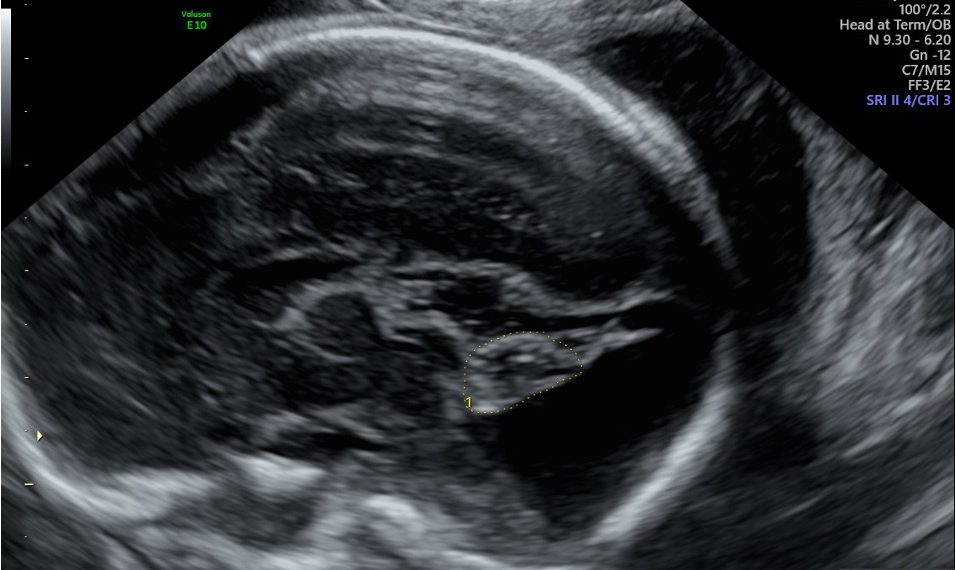

Caso 1 –

Risposta caso clinico SIEOG_Bosco